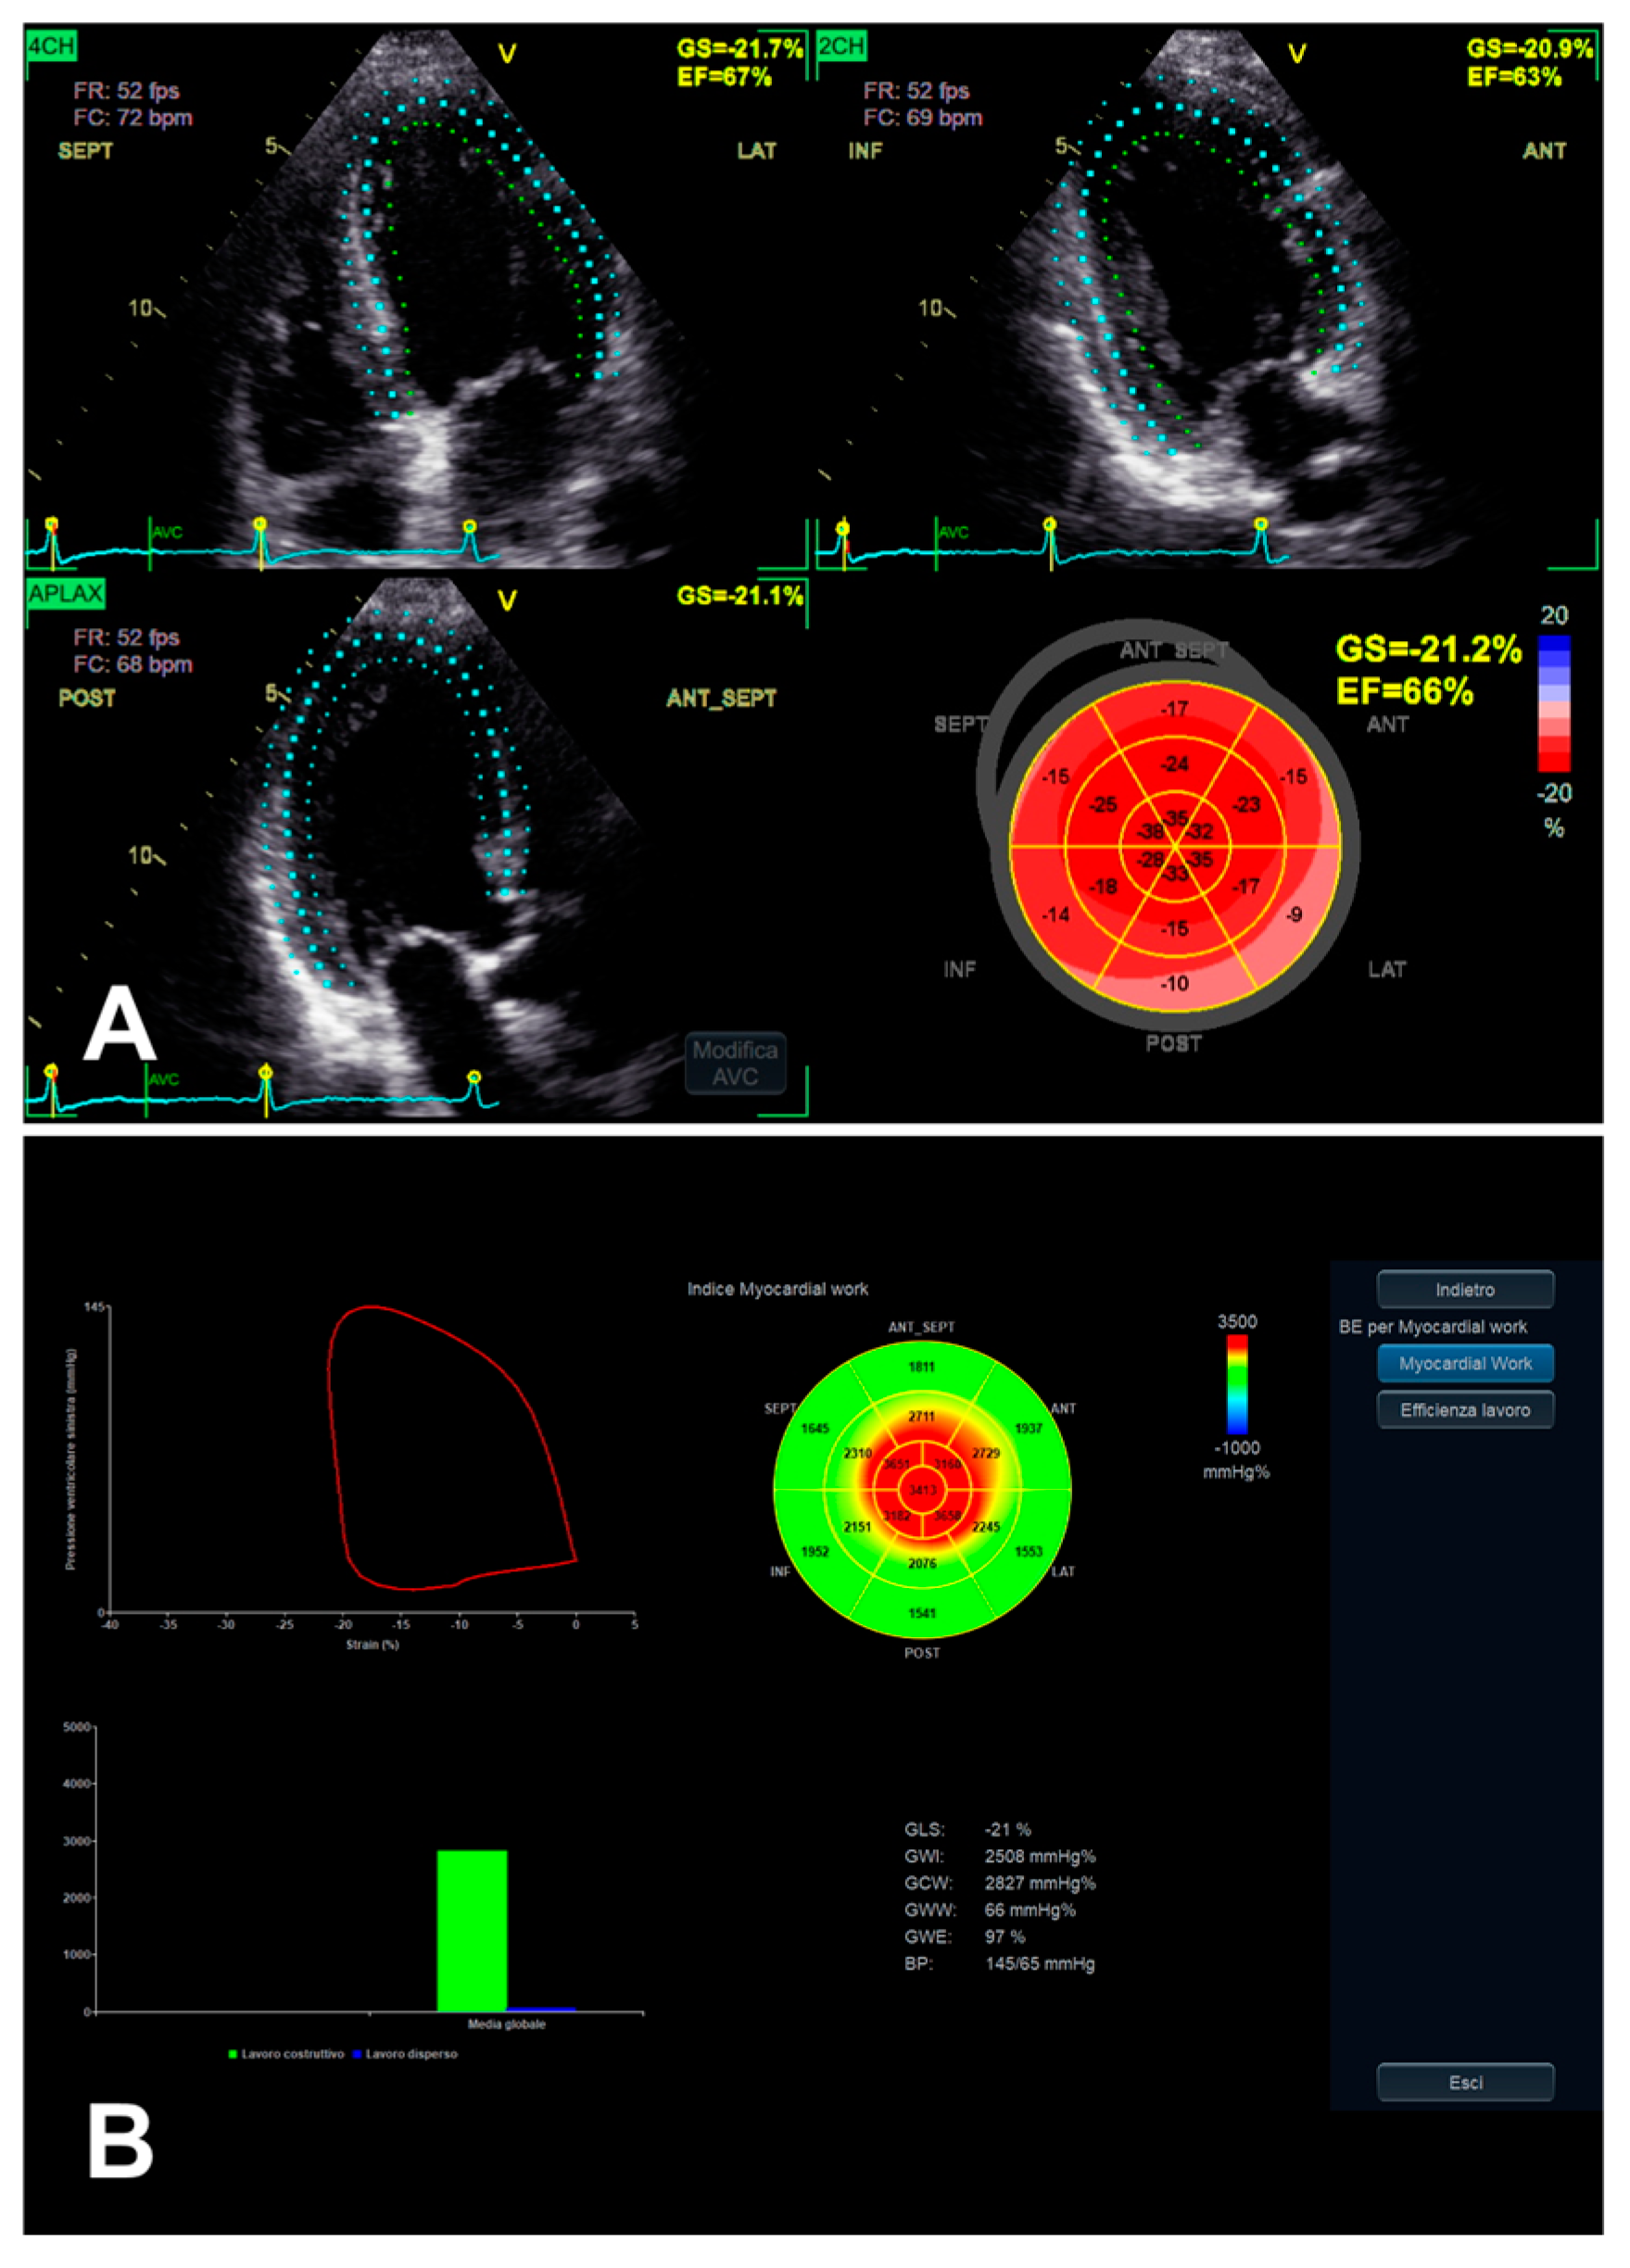

3.1. Left Ventricular Global Longitudinal Strain

3.3. Left Ventricular Myocardial Work

- Dell’Angela, L.; Nicolosi, G.L. From ejection fraction, to myocardial strain, and myocardial work in echocardiography: Clinical impact and controversies. Echocardiography 2024, 41, e15758. [Google Scholar] [CrossRef] [PubMed]

| LV GLS | 2D apical 4C, 3C, and 2C views | Probe in apical zone with 4C, 3C, and 2C views | - Prognostic/predictive value. | - Age and load dependency; - Chest shape dependency; - Image quality-related; - Intervendor and intersoftware variability. |

| LV MW | GCW | Positive work evaluated from AVO to AVC and negative work from AVC to MVO | - Relatively low intra and inter-observer variability (if good US window). | - GLS-related limits (including image quality); - AP measurement-related limits; - Single available software. |

| GWI | Total work evaluated from MVC to MVO | |||

| GWE | GCW/(GCW + GWW) | |||

| GWW | Positive work evaluated from AVO to AVC and negative work from AVC to MVO |